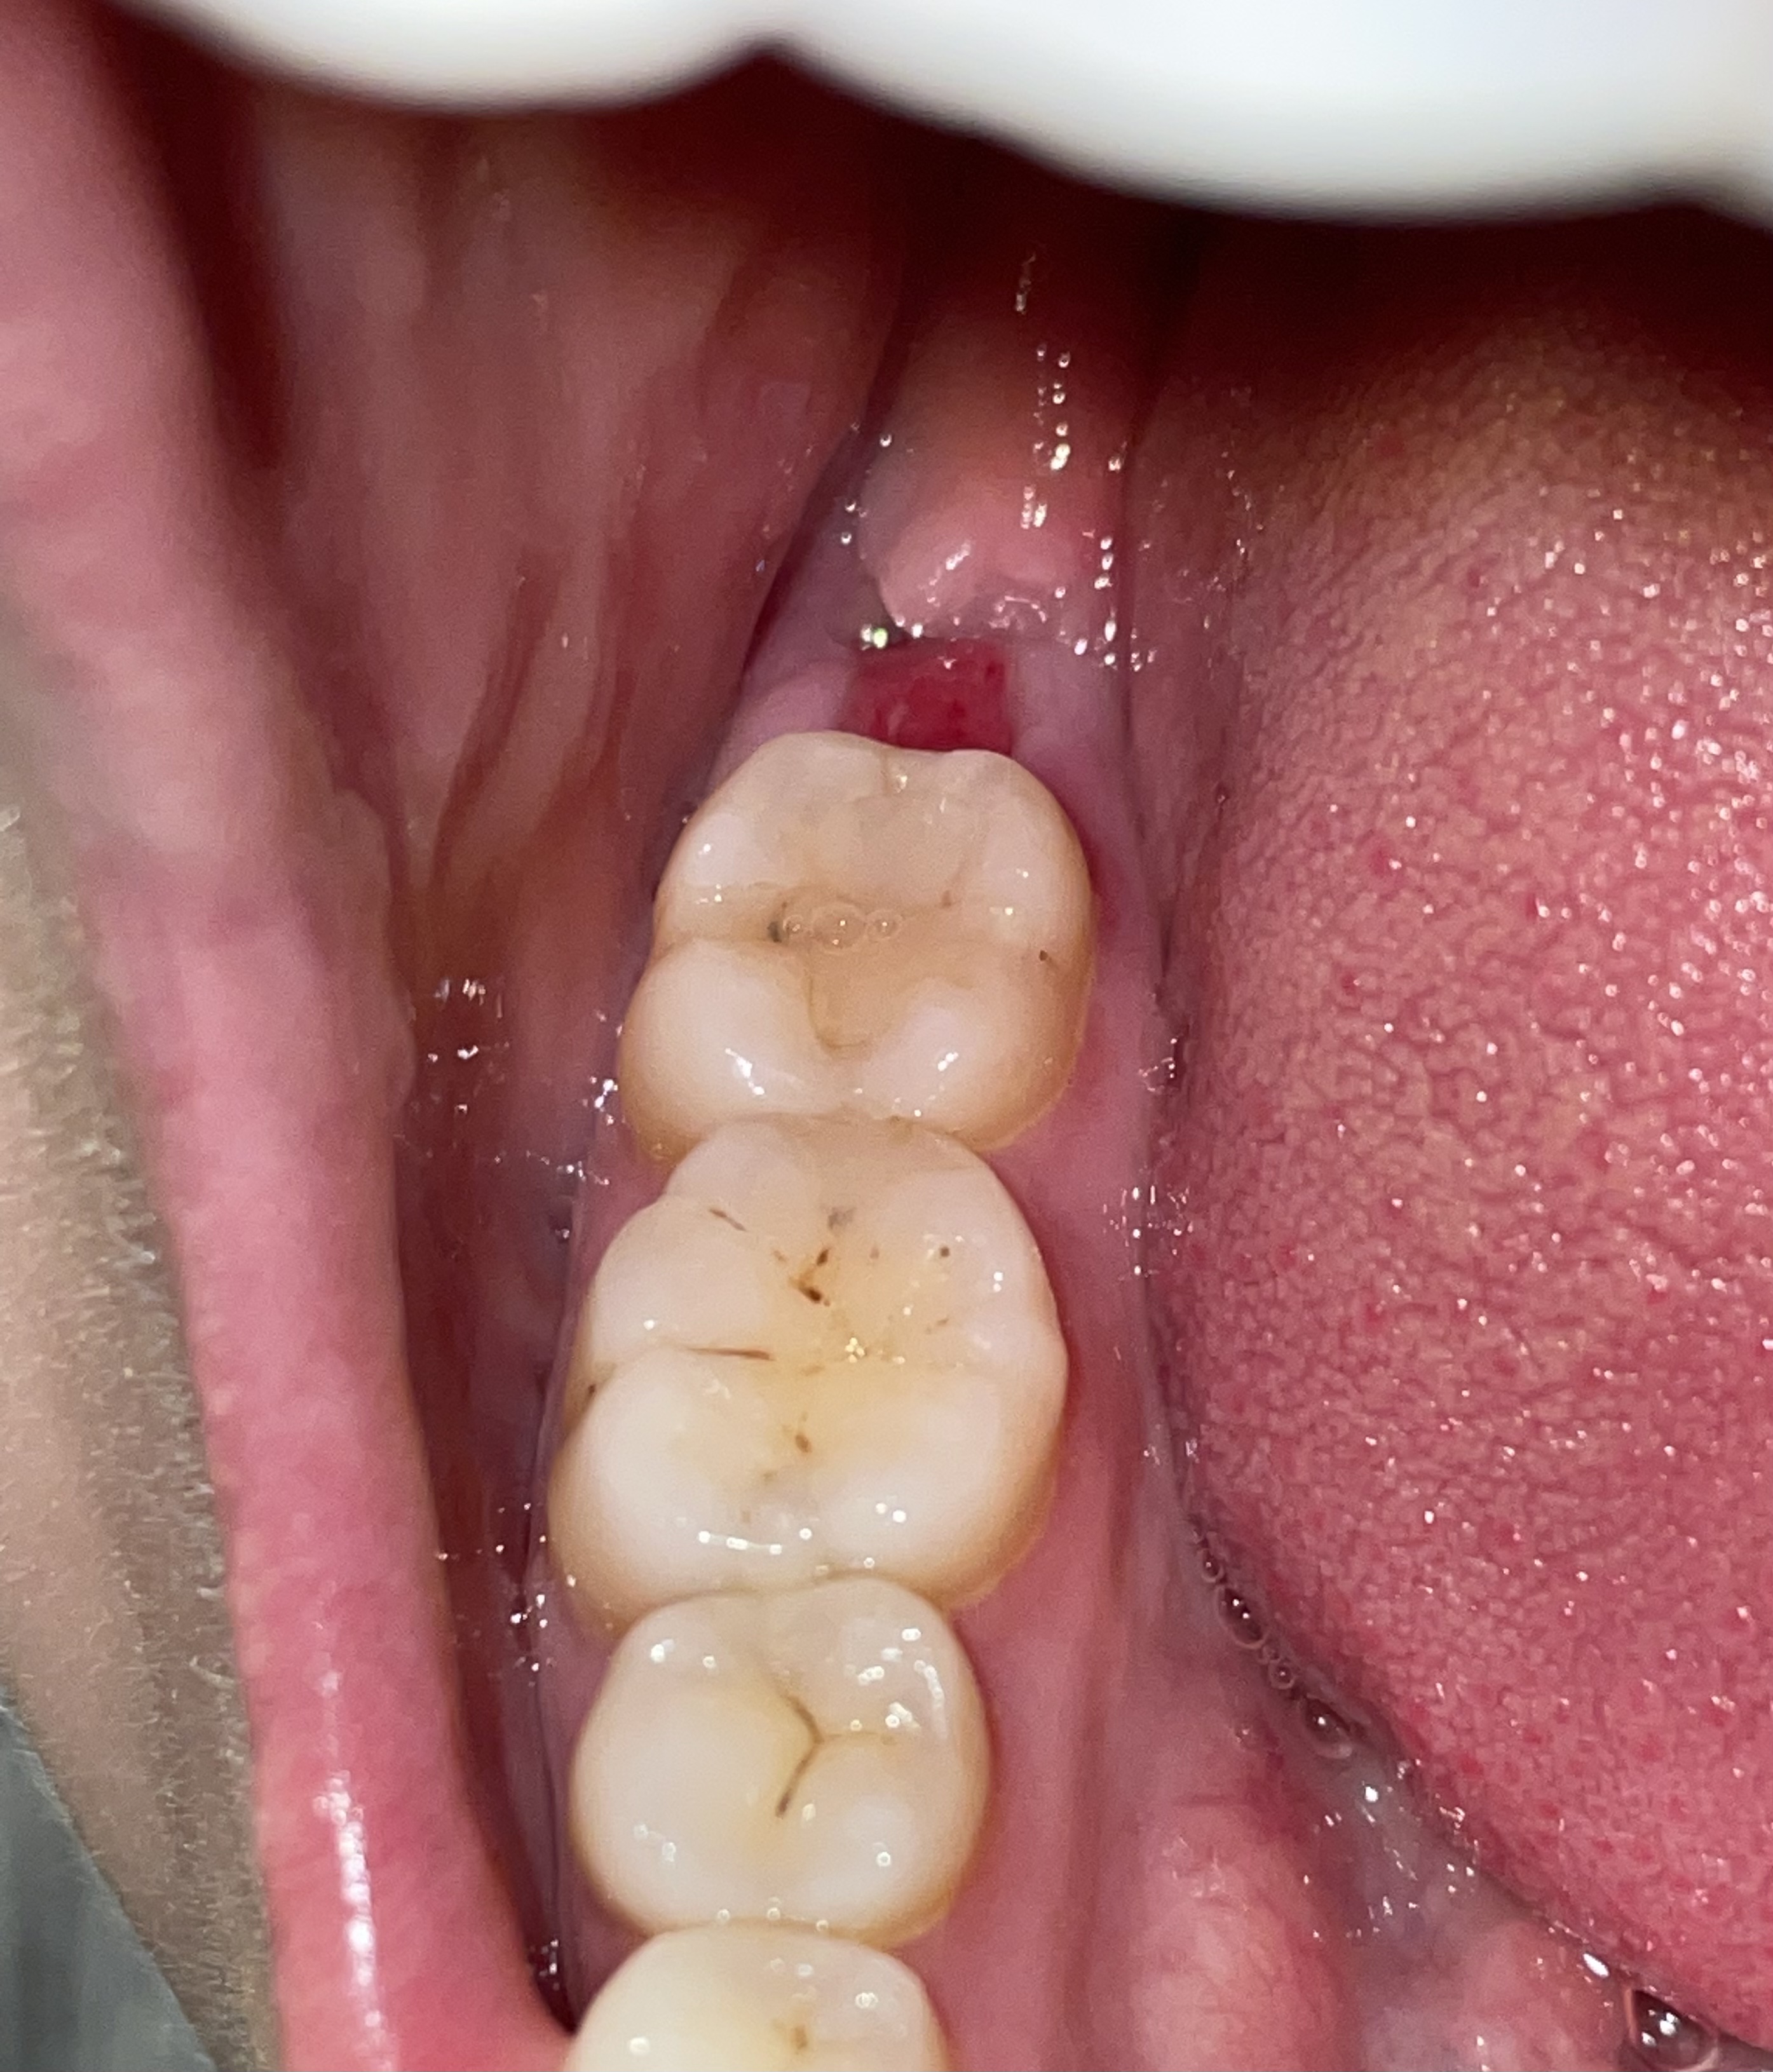

2 weken geleden zijn mijn verstandskiezen rechts getrokken, boven en onder. De napijn en ongemak vond ik tegenvallen, maar sinds een week heb ik geen last meer en sinds een paar dagen heb ik ook niet meer de neiging om steeds in m’n mond te kijken. Het voelt eindelijk weer goed!

Nu leek ik zojuist wel even, en tot mijn grote schrik zie ik roodheid op de plek waar de kies zat. Wat is dit nou? Ik heb geen last meer, het gat is zo goed als dicht, waarom zit hier nu een rode plek! Ik maak me ongerust, kan iemand me hier iets over vertellen?

Granulatie of de granulatiefase is de tweede fase (zie wondfases) in de wondgenezing. Als de exsudatiefase is beeindigd vult de wond zich met nieuw, tijdelijk weefsel. Dit weefsel noemt men granulatieweefsel. Granulatieweefsel is goed doorbloed en ziet er daardoor vrij rood uit.

Dit kan het zijn, maar weet het niet zeker. Ik kijk normaliter in de mond en voel. Kijk het even aan, wil je het zeker weten laat je tandarts het in de mond beoordelen.

Hoe herken je Hypergranulatie?

Echter het komt voor dat er teveel wordt gevormd, zoveel dat het granulatieweefsel boven het niveau van de omliggende huid uitsteekt. Dit wordt hypergranulatie genoemd. Dit is te herkennen aan rode bobbeltjes op het littekenweefsel. Dit kan ook. Laat het dan even beoordelen